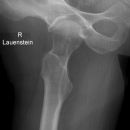

Hüfte axial nach Lauenstein

Epiphysioloysis capitis femoris, M.Perthes bzw. Hüftkopfnekrosen anderer Ätiologie.

Darstellung des Schenkelhalses ohne Verkürzung. Keine Bedeutung für die traumatologische Diagnostik, hier a.p.- und axiale Aufnahme als Basisdiagnostik! Keine überlagerungsfreie Beurteilung des Azetabulums möglich!

Beurteilungskriterien

- Femurkopf (Entrundung, Kondensation, Abrutschen?) und Schenkelhalskontur

- Trochanter major (teilweise über Schenkelhals projiziert) und minor